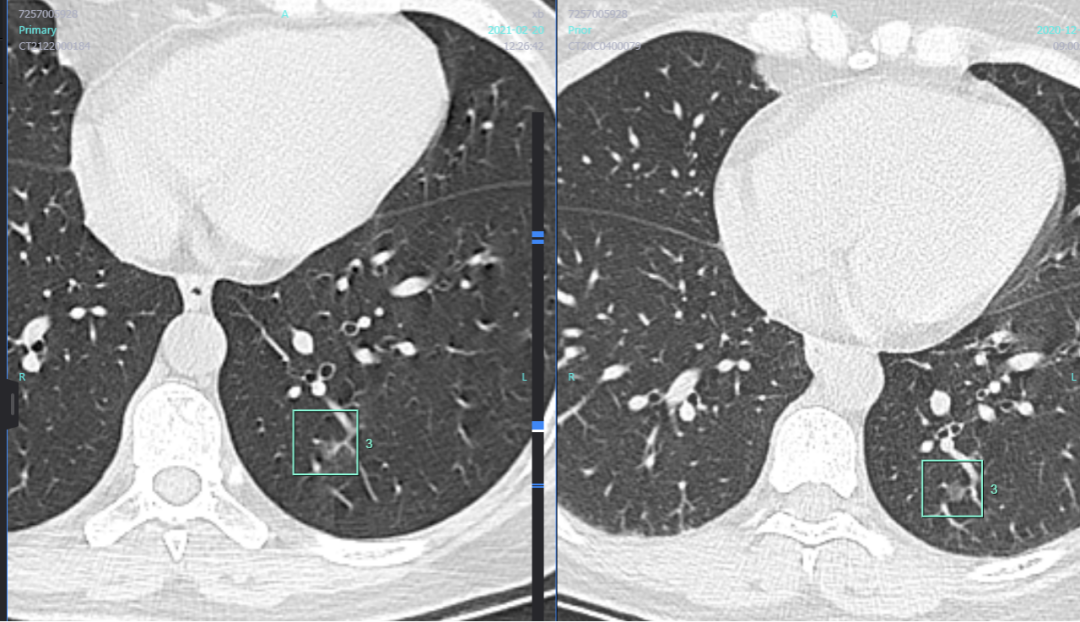

发现肺结节之后,大家听到医生讲的最多的一句话就是随诊观察。焦虑中的患者最想知道的就是,观察到什么时候是个头儿啊?要杀要剐您给句话,天天悬着心那是真难受啊。 首都医科大学附属北京胸科医院影像科主任医师、肺结节诊治中心侯代伦教授说,这就像临阵对敌,首先,自己要沉住气,时间也是个好武器,它迟早会让肺结节暴露真相。 这是一位49岁的女性患者,随访了三个月,对比前后的肺结节变化,影像科、肿瘤科、胸外科联合评估,最终拿出了明确的说法。那么这个肺结节是如何暴露自己的“坏蛋”本性的呢? 三个月前,这枚肺结节中间似乎有空泡,周围有一些小的毛刺和轻度的血管牵拉。侯教授建议她进行三个月的科学随访。 这是三个月以后的复查CT图像。似乎感觉空泡增多,原来有一个空泡,现在有两个空泡;与血管牵拉变得更加明显。 这个牵拉说明什么?说明这个结节有一定的收缩,它对周围的解剖结构有拉力的,这种拉力,单单从影像上很难体会到,需要有经验的医师看片多了以后,沉淀经验,才可能体会出这种拉力。 对比三个月前的CT图像,上图是三个月前,下图是三个月后,拉力明显增强。 这枚结节用计算机测量只有8×7毫米,该如何处理呢? 这时,借助计算机AI测量的两次CT对比结果如下。 这枚结节的体积从155.08立方毫米,到157.57立方毫米。说明三个月的时间里,计算机认为,结节体积增大并不明显。但是,实性部分的占比,从0.72增加为1.38%,比例增加了一倍。所以,侯教授分析认为,这枚结节周围牵拉力增大,实性成分较前增加。是时候对它进行干预了。 这位女性患者只有49岁,因为这枚肺结节导致的心理压力很大,希望积极处理的意愿也很强烈。于是,影像科、肿瘤科、胸外科联合会诊,决定在近期选择胸腔镜进行微创手术。 在CT引导下,放入标志物“钓鱼钩”,勾住后,用胸腔镜进行肺的楔形切除。切除以后,这位49岁的女患者今后的生活质量不会受到明显影响,身体完全可以恢复正常,比她现在的焦虑状态要好得多。 侯代伦教授提醒大家,一定不要见到肺结节就焦虑,见到肺结节就想手术。第一要耐住性子沉住气,三到六个月复查一下,找专业医生进行科学评估,再做决定。